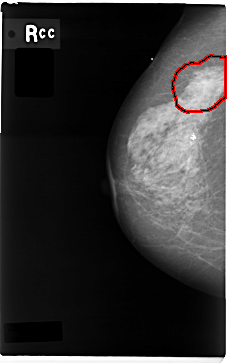

FILE: C_0004_1.RIGHT_CC.OVERLAY

TOTAL_ABNORMALITIES 1

ABNORMALITY 1

LESION_TYPE MASS SHAPE IRREGULAR MARGINS SPICULATED

ASSESSMENT 5

SUBTLETY 5

PATHOLOGY MALIGNANT

TOTAL_OUTLINES 1

BOUNDARY